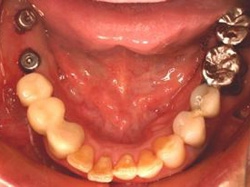

術後(鏡像)

術後口腔内(正面観)もう入れ歯は要らなくなりました。